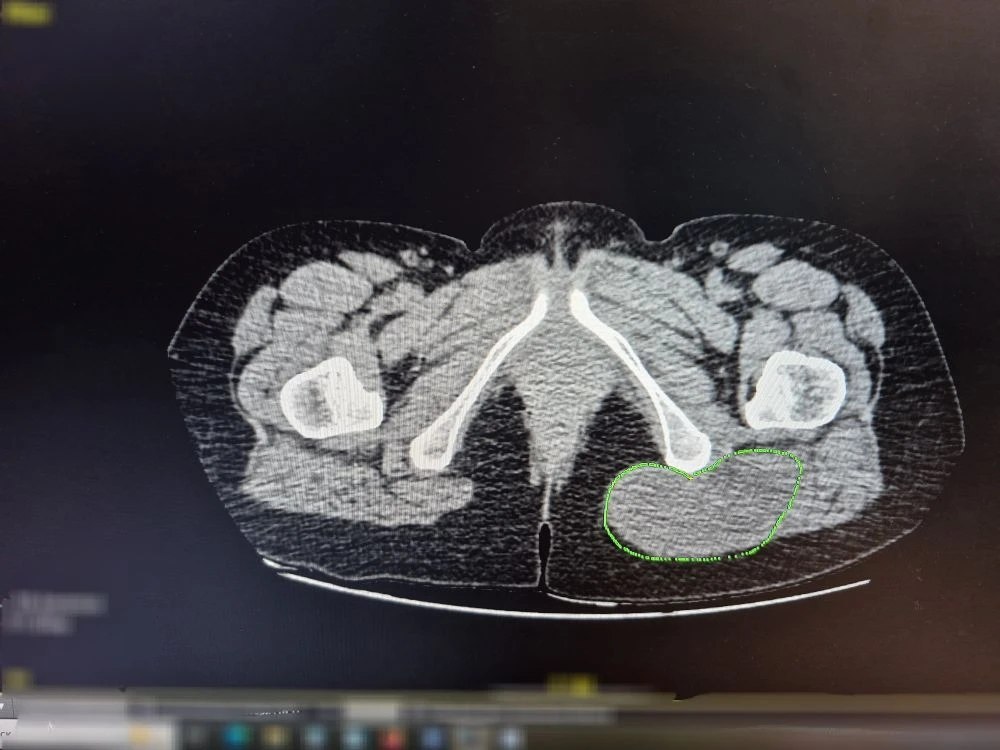

Клиническим случаем поделился заведующий хирургическим отделением Роман Тимохин. Пациентка обратилась в отделение с образованием в области ягодицы. Сначала опухоль была небольшой — около 1 см, но в течение нескольких месяцев начала расти.

Вместо того, чтобы воспользоваться помощью врачей, женщина отправилась на массаж. Массажист, приняв новообразование за обычный застой, попытался размять его мануальными техниками. После этого опухоль увеличиваться и достигла 10 см. Комплексное обследование в больнице показало, что жировик на деле оказался злокачественным новообразованием.

Пациентке сделали операцию. По словам специалистов, у неё есть все шансы на полное выздоровление.